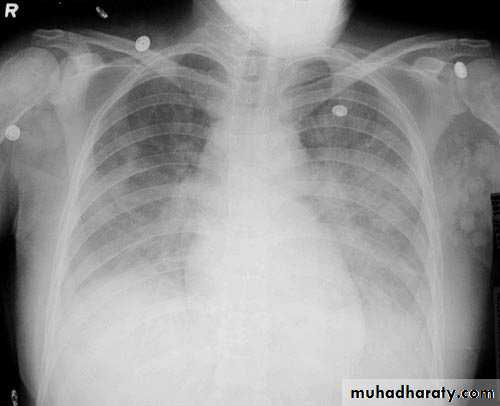

Pneumothorax

Pneumothorax refers to the presence of gas (air) in the pleural space. When this collection of gas is constantly enlarging with resulting compression of mediastinal structures it can be life-threatening and is known as a tension pneumothoraxIt is useful to divide pneumo thoraces into three categories :

primary spontaneous: no underlying lung disease marfan syndrum , Elher danus syndrome alpha-1 antitrypsin deficiency

secondary spontaneous: underlying lung disease is present

iatrogenic/traumatic

Radiographic features

Chest radiographA pneumothorax is, when looked for, usually relatively easily appreciated. Typically they demonstrate:

visible visceral pleural edge see as a very thin, sharp white line

no lung markings are seen peripheral to this line

the peripheral space is radiolucent compared to adjacent lung

the lung may completely collapse

the mediastinum should not shift away from the pneumothorax unless a tension pneumothorax is present

A tension pneumothorax

A tension pneumothorax occurs when intrapleural air accumulates progressively in such a way as to exert positive pressure on mediastinal and intrathoracic structures. It is a life threatening occurrence requiring rapid recognition and treatment is required if cardiorespiratory arrest is to be avoided.Radiographic features

A pneumothorax will have the same features as a run-of-the-mill pneumothorax with a number of additional features, helpful in identifying tension. These additional signs indicate over expansion of the hemithorax:

ipsilateral increased intercostal spaces

shift of the mediastinum to the contralateral side

depression of the hemidiaphragm